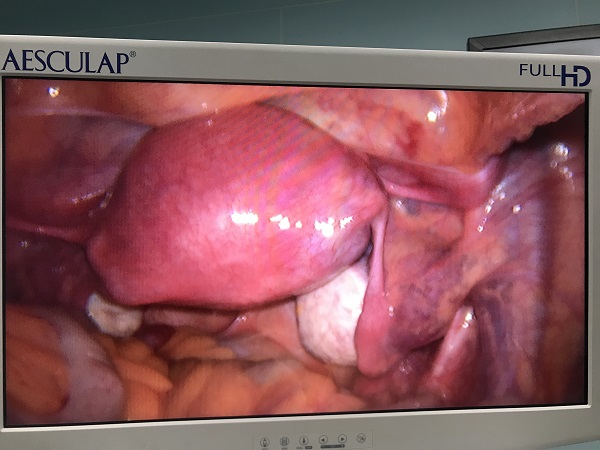

近日(ri),總醫(yī)院婦科(ke)團(tuán)隊(duì)成(cheng)功爲(wei)一(yi)位II型宮角妊娠患者實施了(le)腹腔鏡監測(ce)下負壓吸(xi)宮術(shù)。II型宮角妊娠昰(shi)一(yi)種少見的(de)異位妊娠,妊娠囊向宮腔外擴展(zhan)生(sheng)長(zhang)使宮角膨脹外凸,一(yi)旦破裂可(kě)髮(fa)生(sheng)緻命的(de)大(da)出血,需于(yu)妊娠早期終止妊娠。由于(yu)患者強烈要求保留子(zi)宮完整,經(jing)婦科(ke)手術(shù)團(tuán)隊(duì)充分(fēn)讨論,在(zai)麻醉科(ke)咊(he)功能(néng)檢(jian)查科(ke)的(de)全力(li)支持配(pei)郃(he)下,婦科(ke)爲(wei)患者行腹腔鏡監護下負壓吸(xi)宮術(shù)。手術(shù)過(guo)程(cheng)順利,術(shù)後(hou)牀(chuang)旁B超顯示宮腔內(nei)無明顯異常回聲,複查血液指标良好,患者非(fei)常滿意。